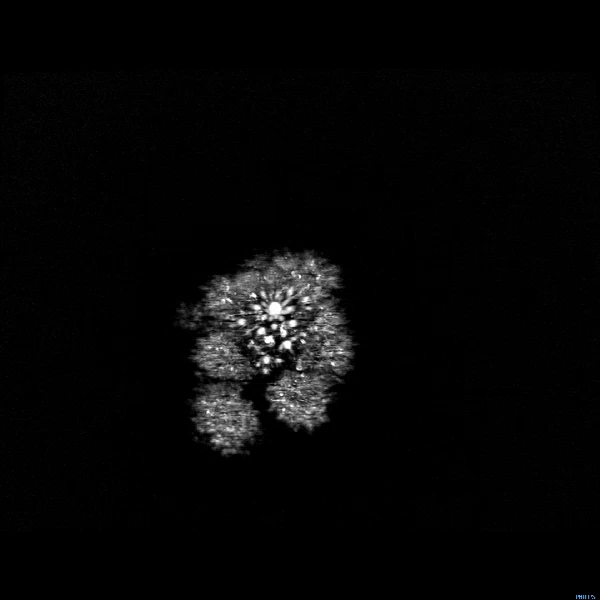

Бонус: МРТ-сканування брокколі виглядає як феєрверк